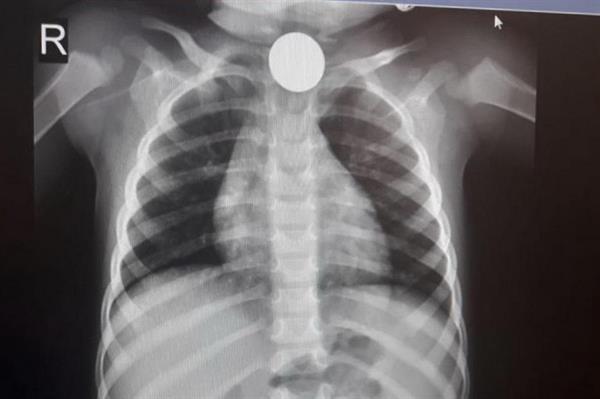

יום לאחר מכן התרחש מקרה נוסף של פעוט בן שנה ועשרה חודשים, שהגיע אף הוא למיון ילדים לאחר שהוריו חשדו כי בלע מטבע של 10 שקלים. ההורים סיפרו כי יום לפני כן שיחק הפעוט עם המטבע ורק ביום למחרת, לאחר שהקיא מספר פעמים, חשדו ההורים שמא בלע את המטבע. בצילום נראה בבירור המטבע בחלקו העליון של הוושט.

"לאחר שהבחנו כי המטבע תקוע בחלק העליון של הוושט, הכנסנו את הפעוט במהירות לחדר הניתוח ובאמצעות אנדוסקופ קשיח – צינור מיוחד המכיל מקור אור, שלפנו את המטבע התקוע תחת הרדמה מלאה", ציינו ד"ר יצחק ברוורמן, מנהל יחידת אף-אוזן-גרון וכירורגיה של ראש-צוואר, וד"ר יצחק שוחט, רופא מתמחה ביחידה. המטבע הוצא בהצלחה על ידי השניים והפעוט נשאר להשגחה למשך יממה ושוחרר לביתו בריא ושלם. ד"ר ברוורמן מדגיש כי הבעיה המסוכנת ביותר היא כאשר גופים זרים נשאפים לריאות, דבר שעלול לגרום לקוצר נשימה בילדים ואף לחנק.